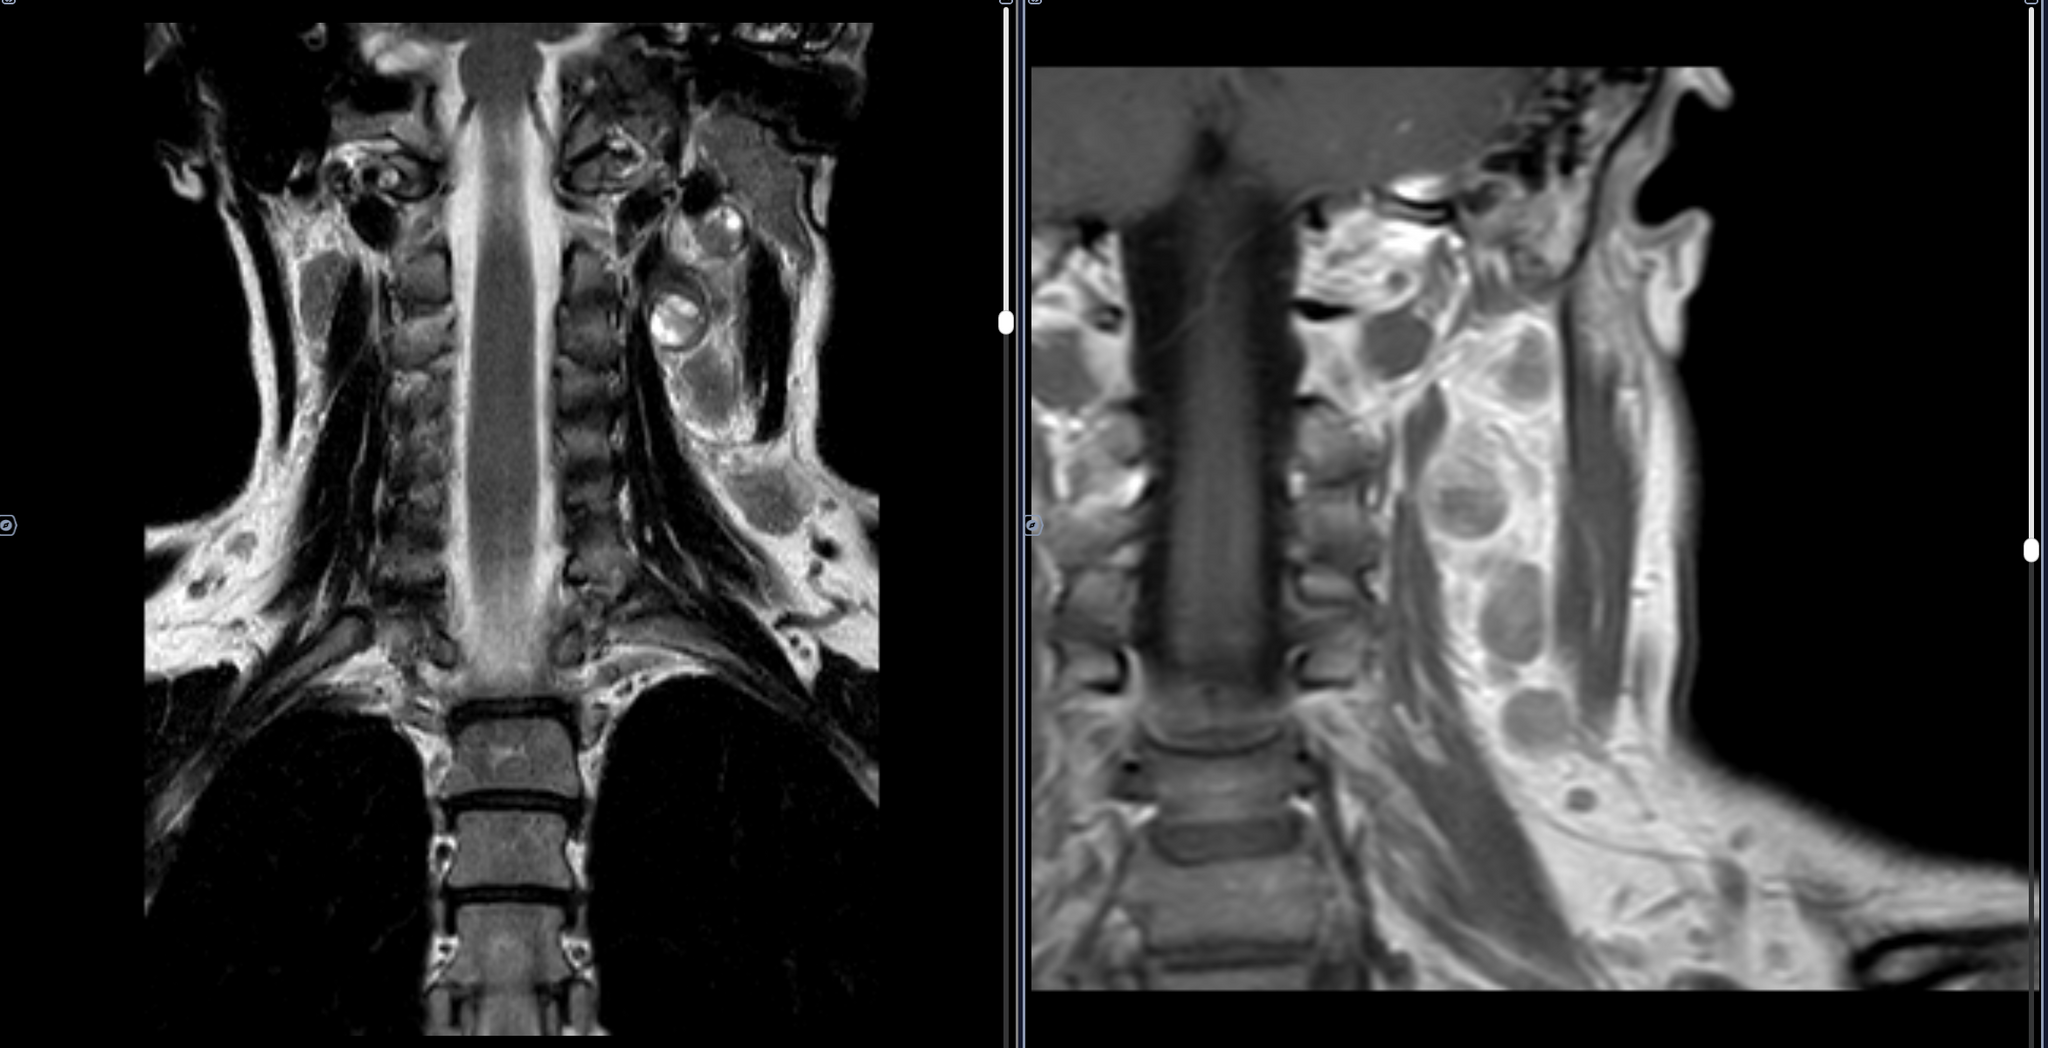

В левом окологлоточном пространстве определяется объемное образование овоидной формы, неоднородной кистозно-солидной структуры, с неоднородным контрастированием, размерами 3,4х2,4х2,3 см.

Определяются увеличенные лимфоузлы боковых поверхностей шеи неоднородной структуры, без врастания в сосуды, размерами до 1,9х1,0х2,0 см справа и до 2,9х2,4х2,4 см слева, с неоднородным контрастированием.

Заключение: МР-картина шейной лимфаденопатии - наиболее соответствует mts. Образование в левом окологлоточном пространстве: злокачественное новообразование/крупный mts в лимфоузел.